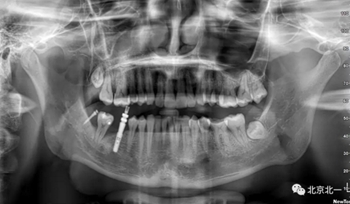

術(shù)后拍片。

正畸支抗直立47

第一次支抗釘脫落, 第二次支抗釘位于48位置, 頰側(cè)舌側(cè)舌側(cè)扣牽引。